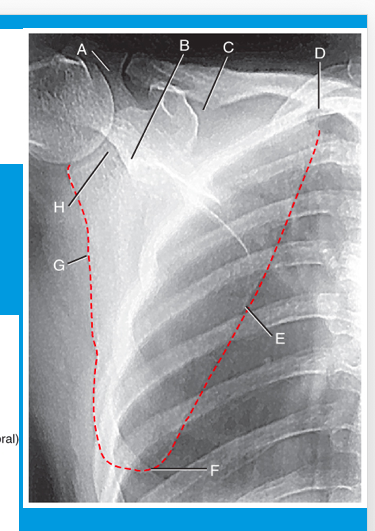

A

neck of scapula

B

suprascapular notch

C

superior angle

D

medial (vertebral) border

E

inferior angle

F

lateral (axillary) border

G

glenoid fossa

H

inferior border